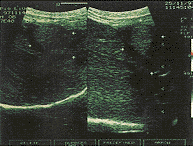

2、HIFU治疗后彩超检测与病理改变 HIFU照射后即刻靶区回声明显增加(图3),解剖大体观:靶区中央可见灰白色凝固性坏死,其周围见暗红色充血区,再外围为苍白色反应带,光镜下可见细胞不可逆性变性坏死。HIFU后1天彩超靶区血供消失、回声增强、边界不太清晰;病检:肝内微血管内皮严重破坏,血管壁塌陷,肝板破坏,肝细胞核固缩。3~7天,靶区回声仍增强,边界清晰,内无血供(图4);病检:靶区呈灰白色改变、质硬、与周围组织界线清晰。光镜下:靶区肝细胞大片坏死,与周围组织分界清楚,在分界处出现炎性细胞、坏死区微小血管破裂。第14天,彩超回声强弱不均,损伤体积缩小;病检:靶区开始收缩、坏死区周围有大量纤维母细胞和新生毛细血管增生。第21天,彩超:体积明显缩小,内部回声以低回声为主;病理:凝固性坏死组织逐渐液化吸收,剖面可见多个或单个小囊腔,壁薄而光滑,内为豆渣样坏死肝组织或清亮液体,镜下见:致密的纤维组织包囊坏死区,并见有大量淋巴细胞浸润。第28天,彩超下损伤区与正常区交界处无显著差异(图5);病检:大体损伤区明显缩小,损伤区基本为新生组织所代替,质地基本与正常肝组织相同,镜下:靶区中心,细胞坏死、自溶,结构完全被破坏,其周边区见假小叶生成,再外围为新生的肝小叶肝细胞形态与排列趋于正常。彩超测定体积与解剖所测损伤区体积基本一致。

靶区中心仍有小片状低回声区为坏死组织液化,其周边区与正常肝组织已无明显区别

图5 在体猪肝HIFU损伤后28d声像图